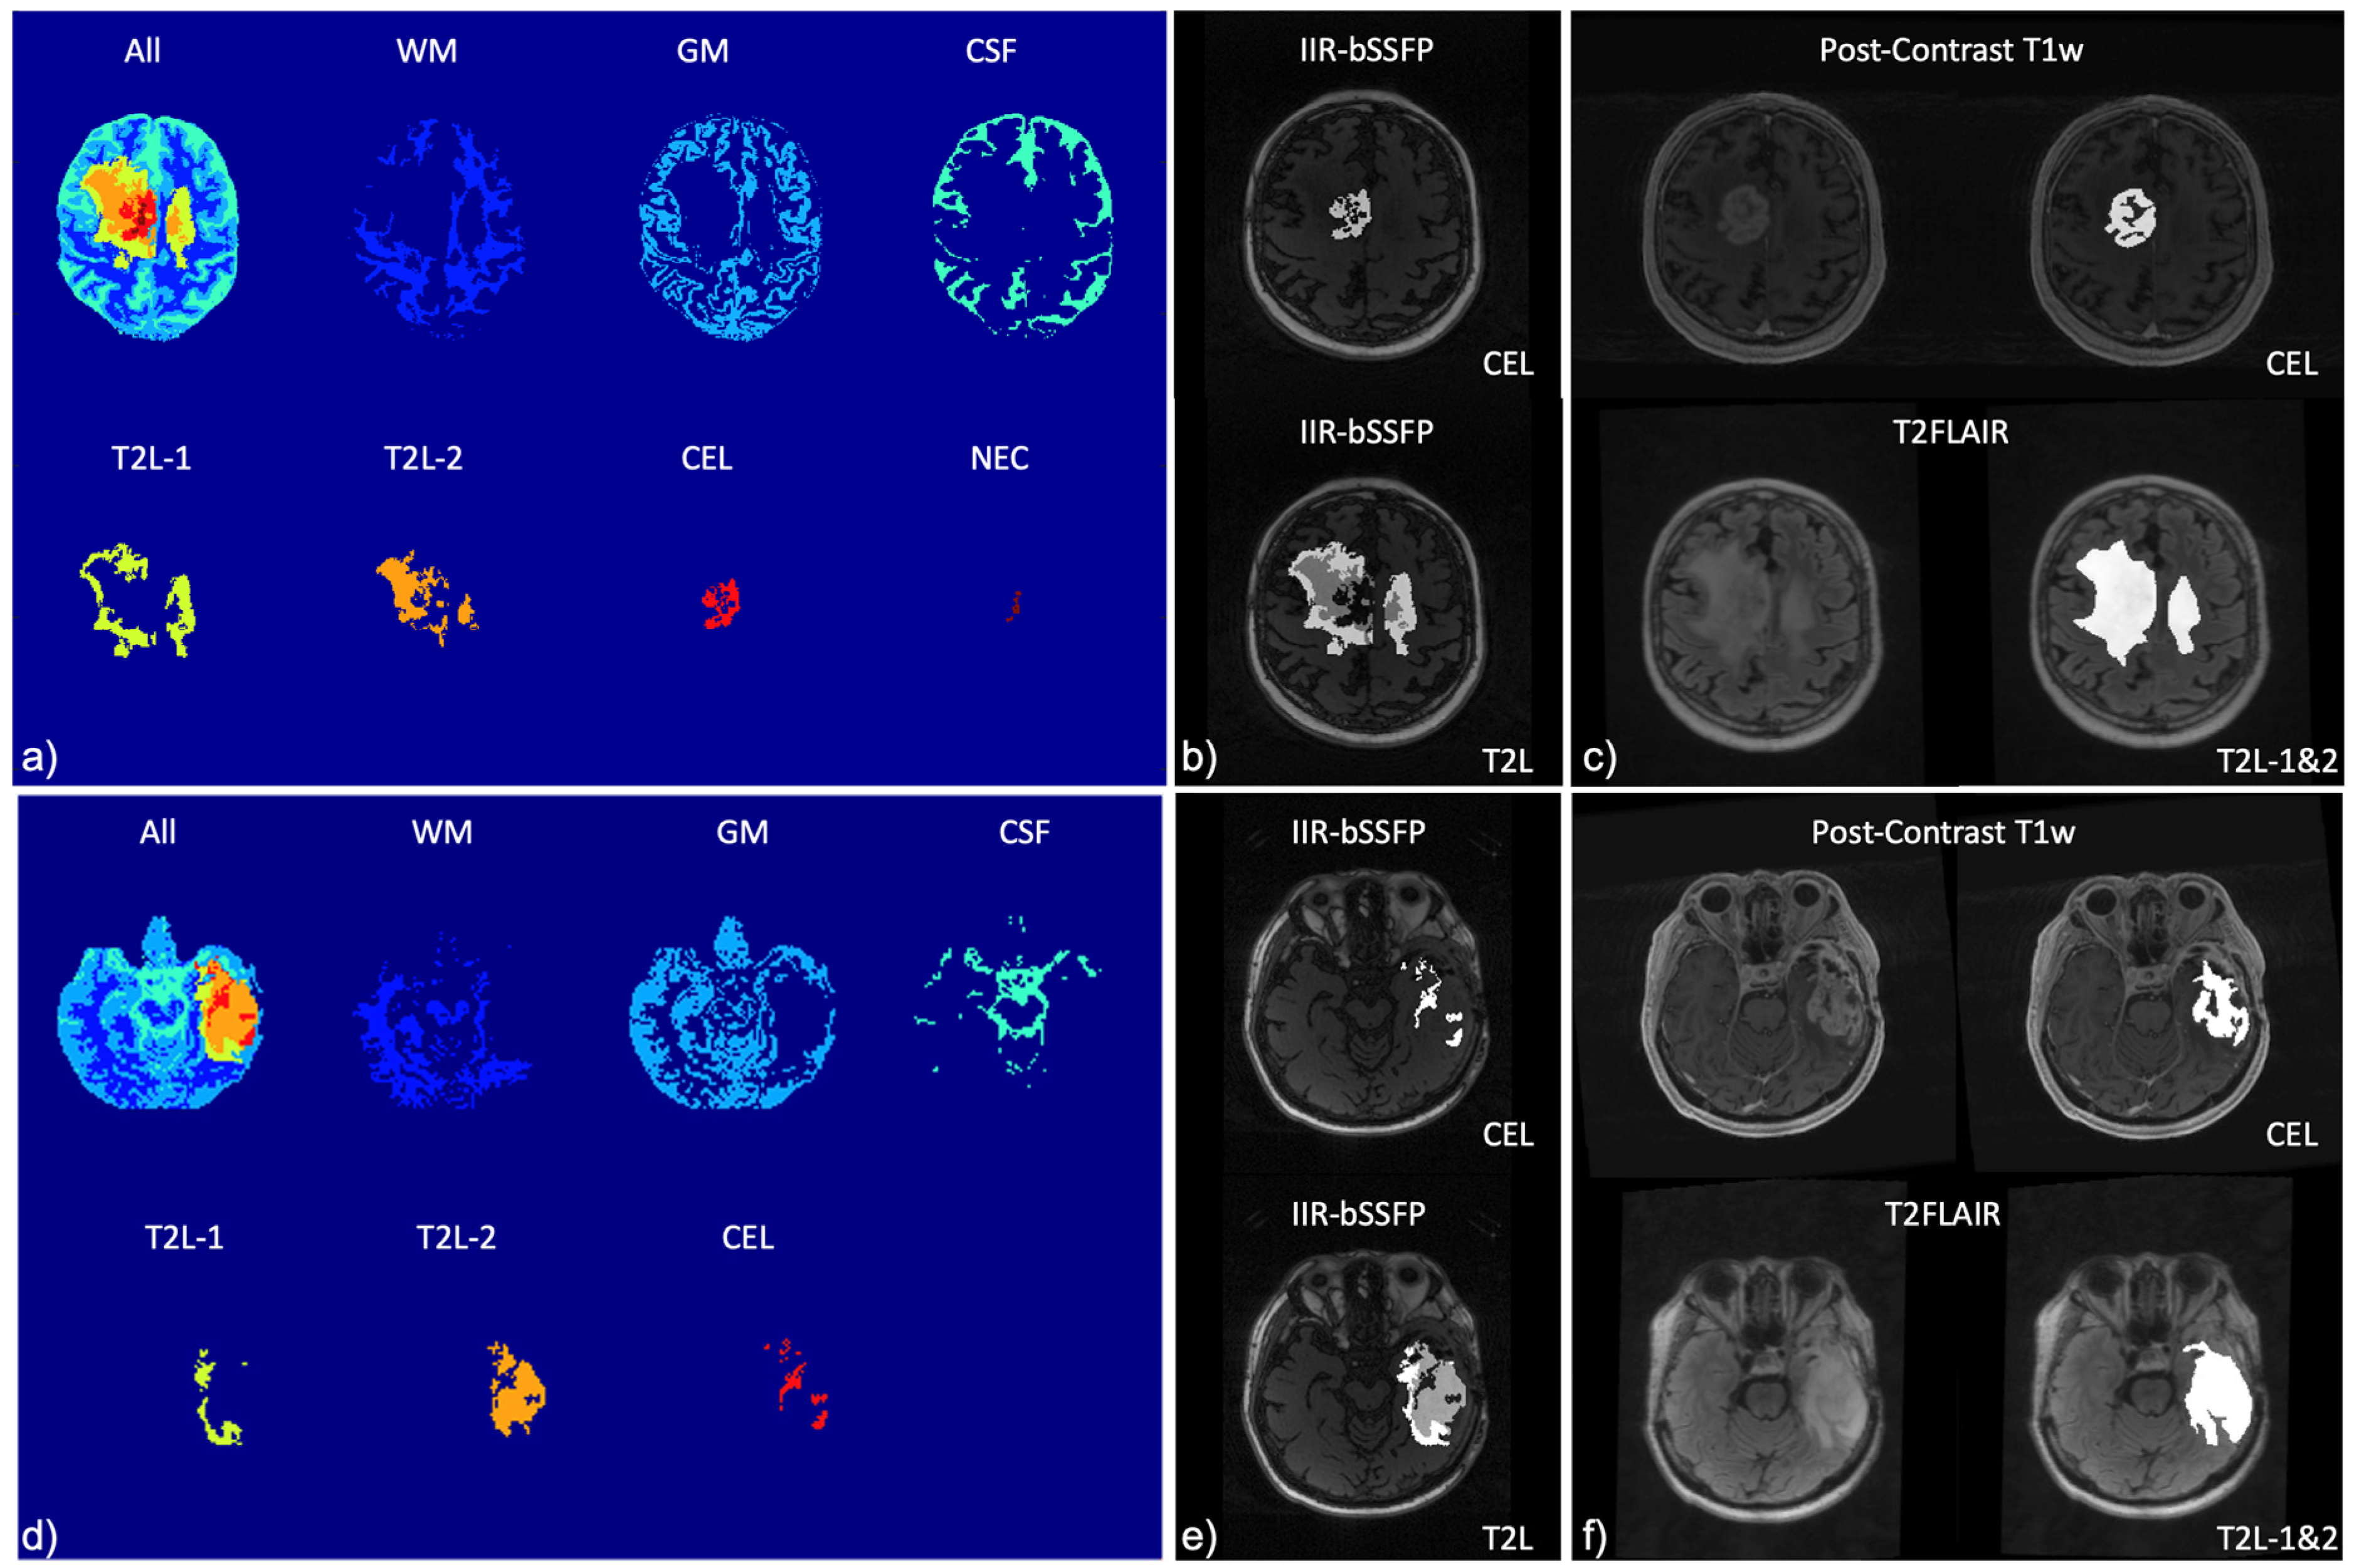

| Mapping | WM | GM | T2L-1 | T2L-2 | CEL | NEC |

|---|---|---|---|---|---|---|

| 2D T1 (ms) | 1186.4 ± 110.5 | 1589.5 ± 331.7 | 1451.5 ± 317 | 1657.9 ± 409.3 | 1947.8 ± 465.6 | 2022.3 ± 459.3 |

| 2D T2 (ms) | 90.4 ± 2.7 | 117.5 ± 12.8 | 114.7 ± 14.2 | 138.2 ± 21.3 | 153.4 ± 47.6 | 152.0 ± 41.1 |

| 3D MWF (%) | 30.4 ± 3.4 | 9.5 ± 3.3 | 12.5 ± 9.3 | 2.3 ± 1.8 | 0.55 ± 0.4 | 0.15 ± 0.0 |

| IIR-bSSFP T1 (ms) | 797.5 ± 88.3 | 670.4 ± 60.2 | 610.9 ± 58.1 | 598.4 ± 77.8 | 958.8 ± 204.9 | 1876.7 ± 608.8 |

| IIR-bSSFP T2 (ms) | 22.0 ± 5.7 | 85.2 ± 8.8 | 62.9 ± 26.5 | 115.4 ± 11.2 | 121.5 ± 10.1 | 157.5 ± 42.0 |

| IIR-bSSFP MF (%) | 14.9 ± 2.5 | 8.7 ± 1.9 | 11.9 ± 3.8 | 5.5 ± 2.6 | 3.6 ± 2.0 | 1.6 ± 0.5 |

| Mapping | CSF | WM | GM | T2L-1 | T2L-2 | CEL | NEC |

|---|---|---|---|---|---|---|---|

| IIR-bSSFP T1 (ms) | 2990.4 ± 277.4 | 848.0 ± 135.5 | 912.4 ± 218.4 | 749.5 ± 217.2 | 883.8 ± 238.8 | 1300.7 ± 303.4 | 2696.6 ± 749.7 |

| IIR-bSSFP T2 (ms) | 218.1 ± 14.9 | 28.5 ± 5.3 | 83.1 ± 20.9 | 62.2 ± 22.4 | 94.1 ± 29.1 | 115.8 ± 19.1 | 190.7 ± 31.9 |

| IIR-bSSFP MF (%) | 1.0 ± 0.4 | 10.0 ± 2.8 | 5.3 ± 1.3 | 7.8 ± 3.4 | 3.4 ± 1.3 | 2.6 ± 1.0 | 2.2 ± 1.2 |